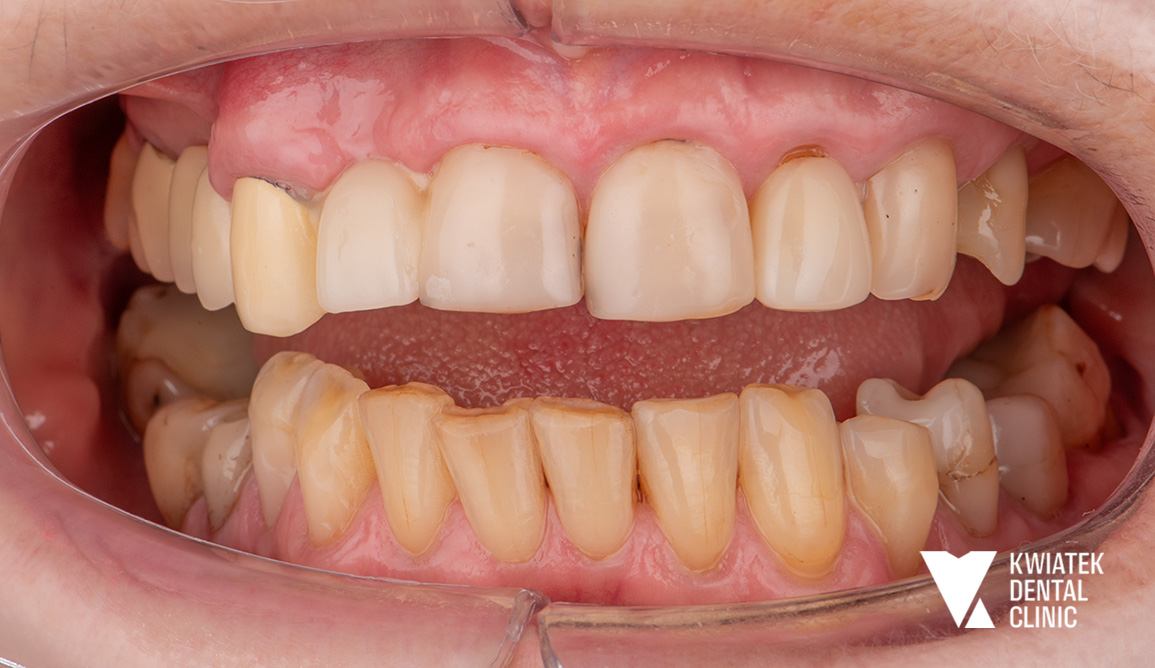

Gdy leczenie staje się sztuką: pełna rehabilitacja jamy ustnej

Do naszej kliniki zgłosił się Pacjent z wieloletnimi, narastającymi problemami stomatologicznymi, obejmującymi liczne ubytki próchnicowe, braki zębowe oraz zużyte, nieszczelne uzupełnienia protetyczne, które przestały spełniać swoją funkcję. Leczenie wymagało precyzyjnie zaplanowanej, wielomiesięcznej terapii obejmującej chirurgię, implantologię, endodoncję mikroskopową oraz rekonstrukcję protetyczną. Finalnie uzyskano stabilną funkcję, wysoką estetykę oraz fizjologiczne warunki pracy narządu żucia.